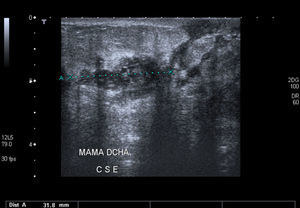

Dieciséis meses, después la paciente continua con MTX a 6mg/semana y 5mg cada 48 h de corticoides, sin presentar recidivas (fig. 3).

La mamografía, la ecografía y la RMN son usadas principalmente para excluir malignidad más que para diagnosticar la mastitis granulomatosa, ya que las imágenes obtenidas no son específicas. La mamografía puede darnos signos indistinguibles de un carcinoma. La ecografía nos puede mostrar una imagen hipoecogénica e irregular con sombra posterior o con la presencia de zonas tubulares. La RMN puede ser útil en la evaluación de la extensión de la lesión y en la evolución. Puede mostrar hipodensidad central, hiperintensidad periférica, lesión heterogénea o una lesión circunscrita con captación heterogénea del contraste2-9.